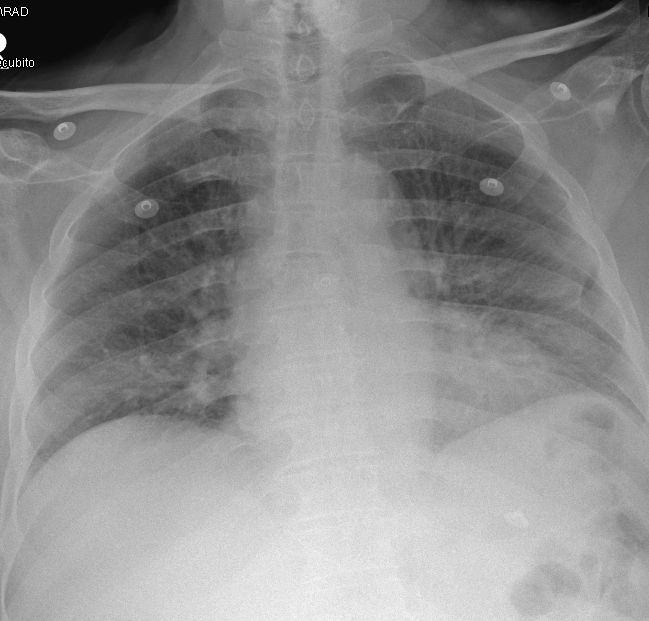

Ecografía diafragmática: se identifica una marcada elevación del hemidiafragma derecho, que se encuentra aplanado con los movimientos respiratorios (imagen 3 y 4) en modo M, compatible con parálisis diafragmática. No se visualiza líquido en fosa de Morrison. El hemidiafragma izquierdo se encuentra normoposicionado con movimientos normales y acordes a la respiración.